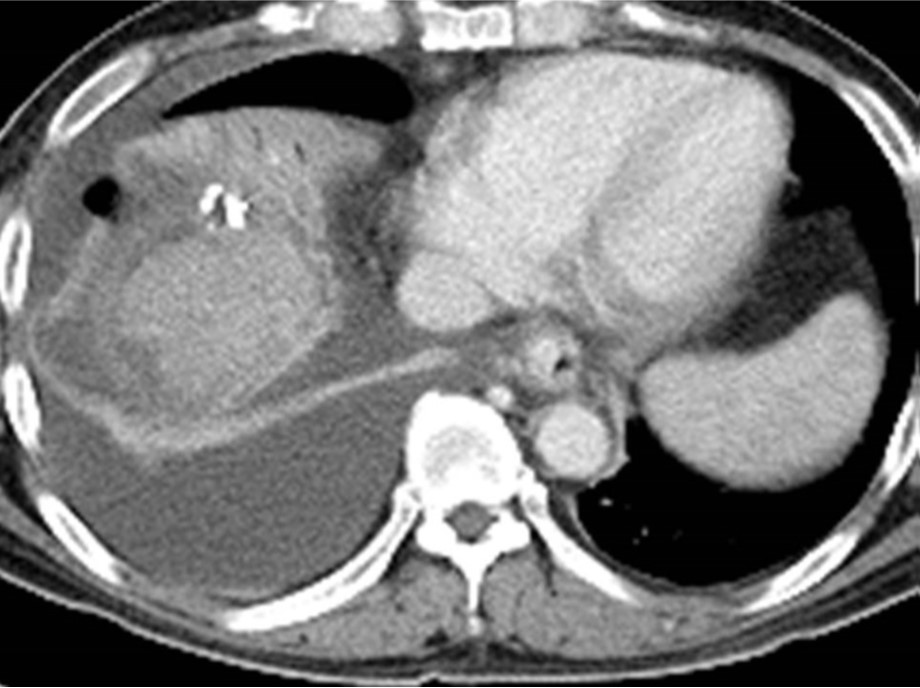

Fig. 1.

Fig. Chest x-ray shows right pleural effusion. Note that PTBD tube was inserted in right intrahepatic duct.

입원 당시 흉부 방사선촬영에서 우측 하부 폐야에 경화소견과 우측 흉막 삼출 소견 보임.